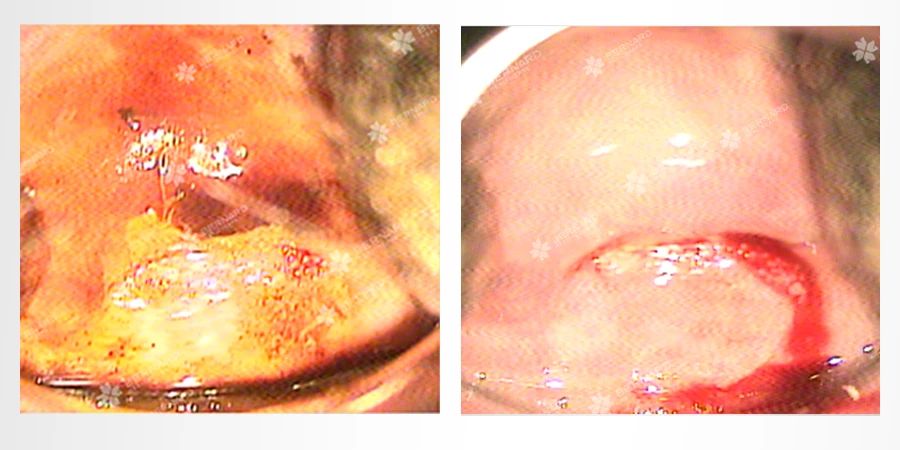

Soi cổ tử cung: Sau thử phản ứng Acid xuất hiện mảng trắng tại vị trí 7h sát lỗ ngoài cổ tử cung. Tiếp tục thử với dung dịch Lugol nhận thấy màu nâu không đều, kết luận có vết trắng cổ tử cung.